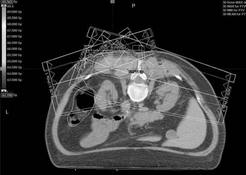

Obr. 1

Technika IMRT u sarkomu uloženého paravertebrálně

Pro nádory v blízkosti míchy je vhodná technika

intenzitně modulované radioterapie (IMRT). Tato technika je vysoce

konformní a umožní aplikaci vyšších dávek záření bez překročení

toleranční dávky míchy (obr. 1). Pro aplikaci vysokých dávek záření